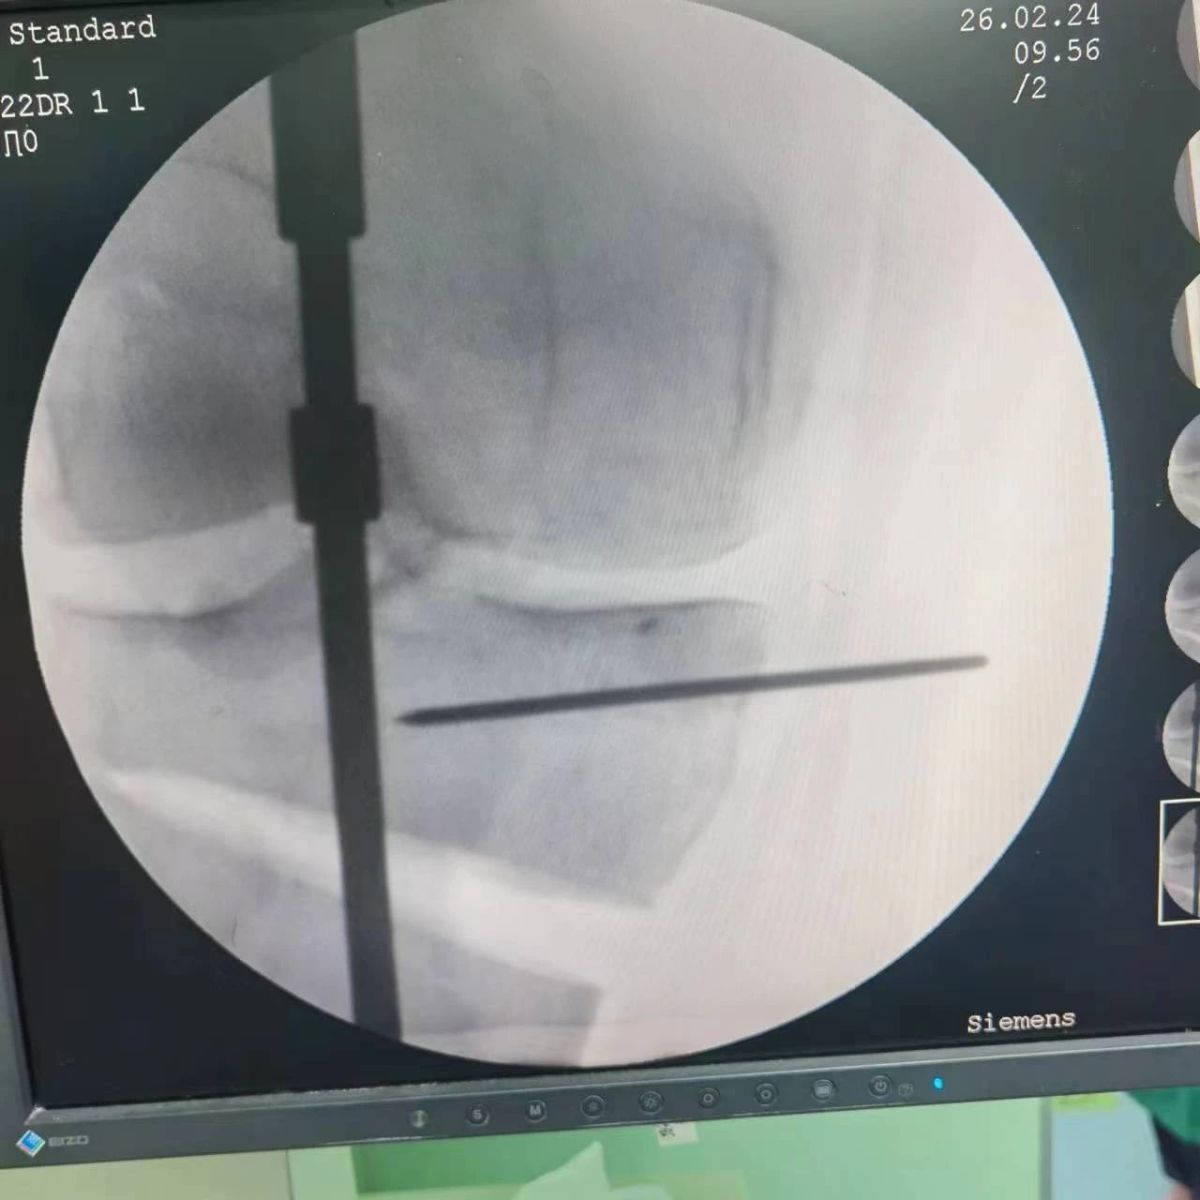

2月26日,漯河市骨科醫(yī)院(漯河醫(yī)專二附院、漯河市立醫(yī)院)膝關節(jié)外科、運動損傷科(骨六科)在保膝治療方面取得了新的突破,李付彬主任帶領岳龍等團隊醫(yī)師,順利完成“計算機精準術前規(guī)劃聯(lián)合3D打印截骨導板輔助脛骨高位截骨治療膝關節(jié)骨性關節(jié)炎”的手術,這在漯河市尚屬首例!

患者為一名45歲男性,查體及X片可見明顯的膝內(nèi)翻,內(nèi)翻畸形主要來源于脛骨近端,關節(jié)鏡下可見內(nèi)側(cè)間室軟骨全層磨損,疼痛較重,年紀輕輕幾乎喪失工作能力。對于這種日?;顒有枨蟊容^大的患者朋友,我們盡最大可能給予保膝治療,李付彬主任給患者詳細講解了保膝治療的方案(脛骨近端高位截骨)及預期效果,給患者帶來了極大希望。為了更精確、更微創(chuàng)的治療,李付彬主任團隊緊跟國內(nèi)外科技前沿,采用計算機精準術前規(guī)劃,并設計3D打印截骨導板,力求給患者帶來更精準、更安全的手術效果。

李付彬主任團隊通過精準術前規(guī)劃,設計目標力線及調(diào)整撐開角度,轉(zhuǎn)化成需要撐開的高度,最終設計出同等高度的填充塊,術中驗證力線調(diào)整與術前規(guī)劃完全一致!

鋼板位置、螺釘位置及長度均可通過術前規(guī)劃計算,術中通過定位操作,基本與術前規(guī)劃一致,手術快速高效完成,外側(cè)合頁保留完整。無任何并發(fā)癥出現(xiàn)。術后見鋼板位置及力線糾正近乎完美!

OWHTO手術效果依賴于多個數(shù)據(jù)參數(shù),比如:截骨的入點、合頁位置的選擇、截骨線的深度、截骨線的方向、撐開的距離等,依托計算機術前精準規(guī)劃和3D打印導板可輔助醫(yī)生精準控制上述參數(shù),使截骨更準確,真正達到精確的力線調(diào)整,減少術中透視次數(shù),縮短手術時間并降低手術風險,從而使得OWHTO得到更好的應用,造?;颊摺?/div>